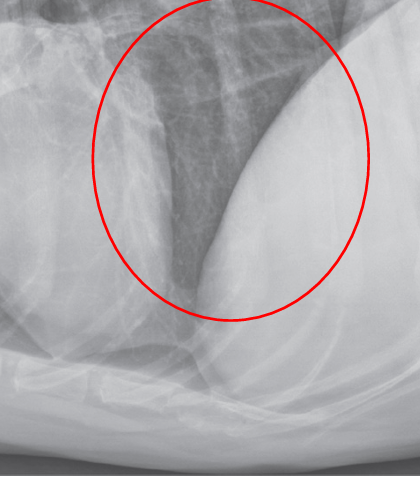

Interstitial pattern

aorta and vena cava is blurry